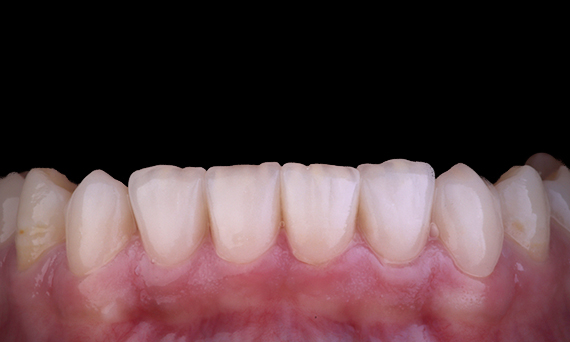

Amelogenezis İmperfekta

28 tamamen seramik restorasyon ile tam ağız rehabilitasyonu

Protez rehabilitasyonu için bir gençte özel ve uzun süreli bir iskelet Sınıf II maloklüzyonu ve jeneralize amelogenezis imperfekta vakası sevk edilmiştir. Tedavinin amacı; kalan diş yapısını hazırlamak, alt kesimleri çıkarmak ve tüm dentini kaplayan ve kayıp mineyi simüle eden tamamen seramik kuronlara yer açmaktı.

Önce: Ortodontik tedaviden önceki ilk durum.

Sonra: Nihai sonuç, ameliyattan 1 hafta sonra.

Alexander Declerck, (DDS, MSc)

Sint-Martens-Latem, Belçika